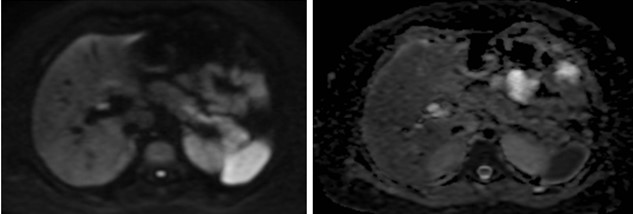

Caso 2

Paciente femenina de 48 años de edad que ingresa a Hospital Sanatorio Franchin por síntomas de cefalea y mareos, cuadro que se hace progresivo, presentando síncopes y posteriormente alteración del estado de conciencia. Los exámenes clínicos revelan una glucosa de 40 mg/dl, concomitante con insulina alta y péptido C elevado. Ingresa de forma programada para realización de duodeno pancreatectomía el 29 de mayo de 2021. Imágenes diagnósticas muestran estudio trifásico de tomografía de abdomen, lesión nodular en la cabeza del páncreas con ávido realce en fase arterial que en resonancia magnética se observa hiperintensa en T2, presenta restricción con la difusión y caída de la señal en el ADC. Además presenta realce tras la administración de contraste con gadolinio.

Estudio histopatológico reveló tumor neuroendocrino bien diferenciado grado 1.

La resonancia magnética es el otro estudio de imagen no invasivo que nos permite la detección de la lesión con una sensibilidad mayor que la de la tomografía, del 85% al 95%, donde los insulinomas presentan un realce tras la administración de contraste con gadolinio y secuencias T1 sin contraste son lesiones hipointensas y en secuencias T2 son hiperintensas.

La resonancia magnética confirmó aún más el diagnóstico de las lesiones ya previamente visualizadas en tomografía en esta revisión, con realce de las lesiones en secuencias T1 y contraste con gadolinio, y en las secuencias funcionales con restricción de la lesión y caída de la señal en el mapa de ADC.